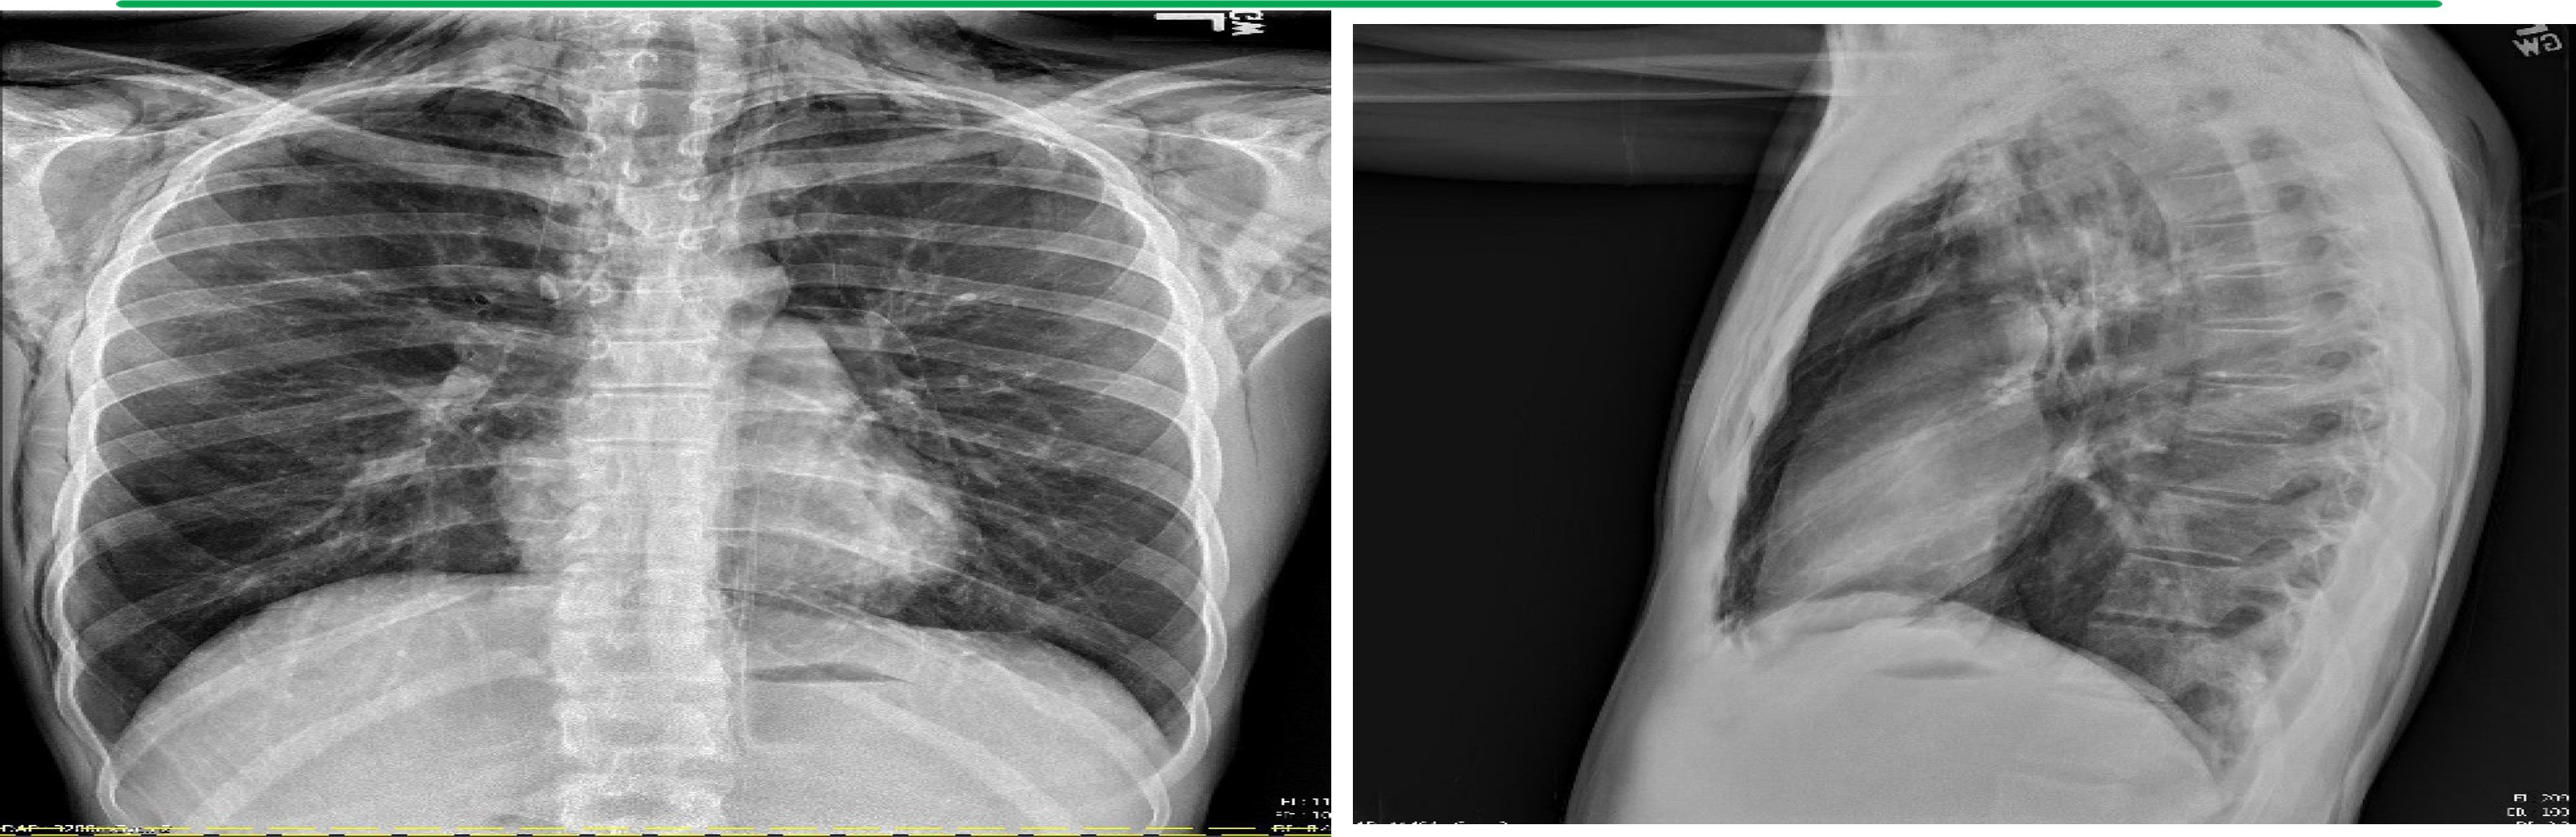

Initial Chest X-ray

Findings: There is extensive pneumomediastinum with air dissecting along the esophagus, mediastinum, and supraclavicular soft tissues, along the lateral chest wall bilaterally, greater on the right.

No definite pneumothorax is visualized.

There is no focal consolidation. There is no pleural effusion. The heart size is normal. The bones are unremarkable.

Impression: Marked pneumomediastinum with air dissecting across the soft tissue planes.

Anterior-Posterior (AP) and Lateral Chest X-ray